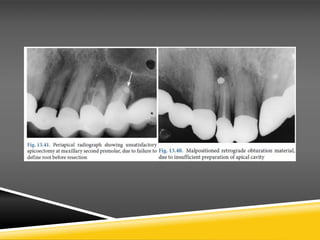

• Splattering of amalgam at the operation site, due to inadequate apical isolation

and improper manipulations for removal of excess filling material

• Dislodged filling material due to superficial placement, as a result of insufficient

preparation of apical cavity

• Incomplete root resection, due to insufficient access or visualization and misjudged

length of root .As a result, the apical portion of the root remains in position and the

retrograde filling is placed improperly, with all the resulting consequences